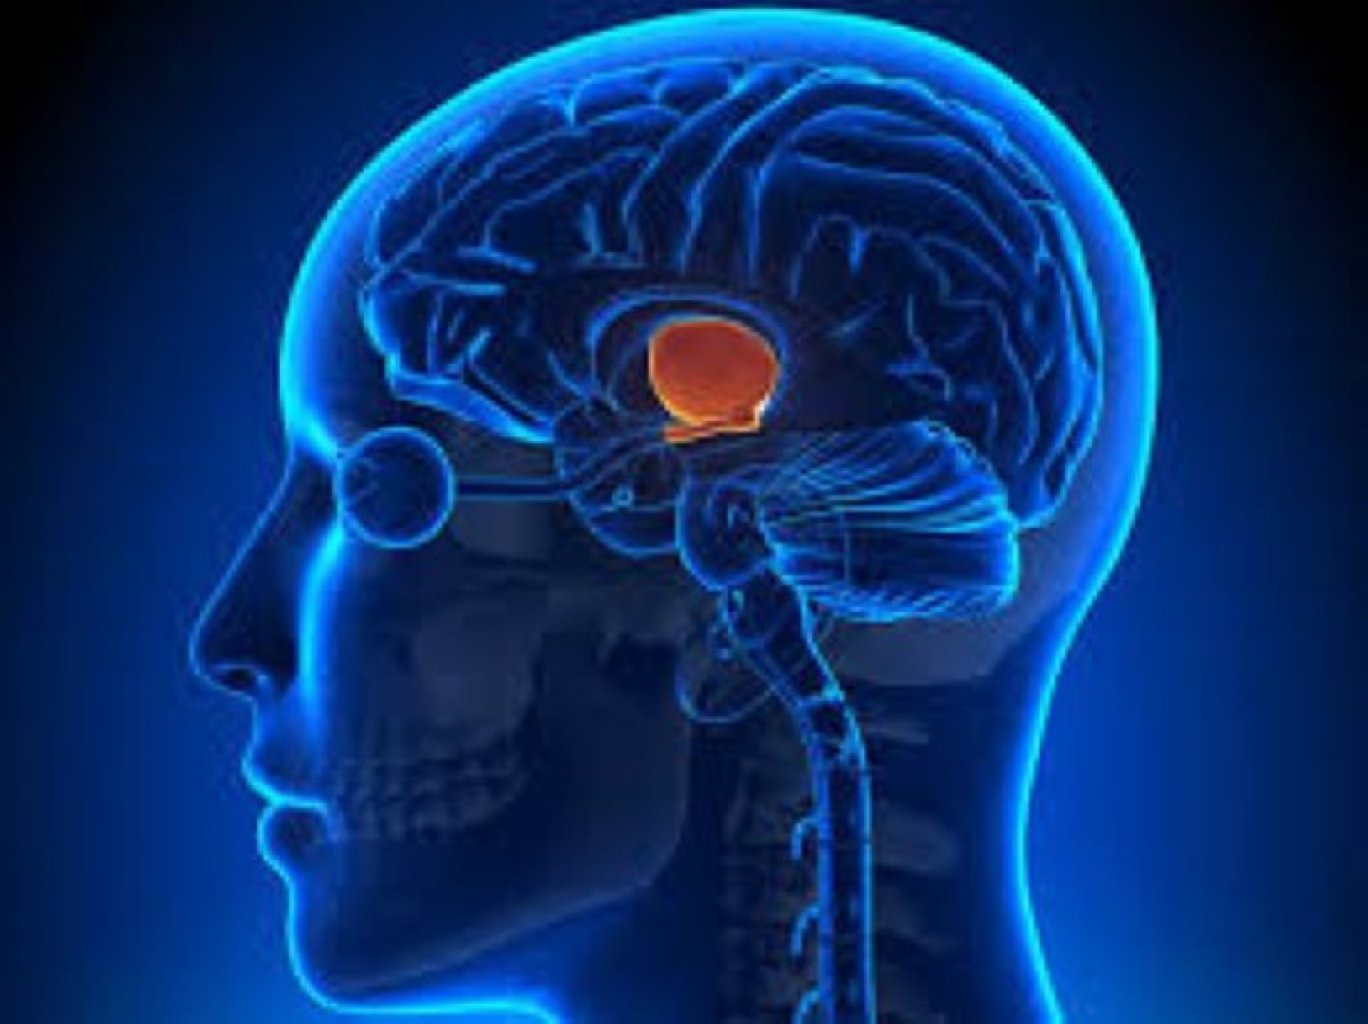

Hipofiz adenomaları: Bu, hipofiz vəzində baş verən tümör və lezyonlardır. Adenomalar, hipofiz vəzi t ...

Hipofiz Vəzi Pozuntularının Növləri Hipofiz Adenoması: Hipofiz vəzində yaranan iyi xassəli şiş ...